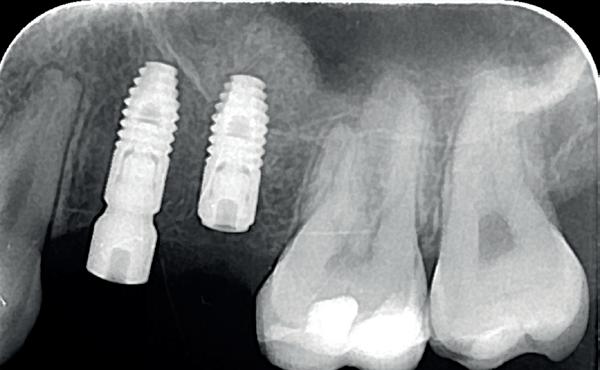

Casus

In deze casus is extractie van de 37 geïndiceerd in verband met een fistel en restpockets, zoals zichtbaar op de röntgenfoto’s (afbeelding 1). Duidelijk te zien is de forse peri-apicale ontsteking en het botverlies bij de 37, dat zowel richting buccaal als linguaal doorloopt. De 37 wordt atraumatisch verwijderd. Er is aan de linguale zijde veel bot verloren en er is sprake van een perforatie aan de buccale zijde.

Er wordt besloten om botmateriaal te plaatsen in de extractie-alveole. Vervolgens wordt het afgesloten met een titanium versterkt d-PTFE membraan (afbeelding 2). Na vier weken wordt het membraan verwijderd.

Zes maanden na extractie wordt het implantaat 37 geplaatst. Er is sprake van een goede genezing en de processushoogte en -breedte zijn behouden en opgebouwd. Ook is er zichtbaar gekeratiniseerd weefsel

1 2 Ridge preservation met d-PTFE membranen 35

gewonnen. De wond kan na het plaatsen van een healing abutment primair gesloten worden (Afbeelding 3a-3d).

In afbeeldingen 4a-c is het resultaat drie maanden na het plaatsen van het implantaat te zien. De genezing is volledig en de verwijzer kan de suprastructuur vervaardigen (afbeelding 4a-4c).

In afbeeldingen 5a-d is de implantaatkroon 37 te zien, twee jaar na plaatsing. Op de röntgenfoto is herstel van zowel corticaal als spongieus bot te zien. (De CB-CT was vervaardigd in verband met implantologische indicatie in het naastliggende gebied).